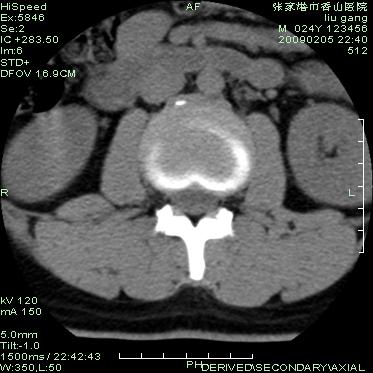

以下是引用随光逐影在2009-3-11 14:43:00的发言:[br]平片:l3、4、5及s1前上缘见类似“切角征”。[br]ct扫描:腰椎多个节段椎间盘向椎体内(椎体前部)突出。